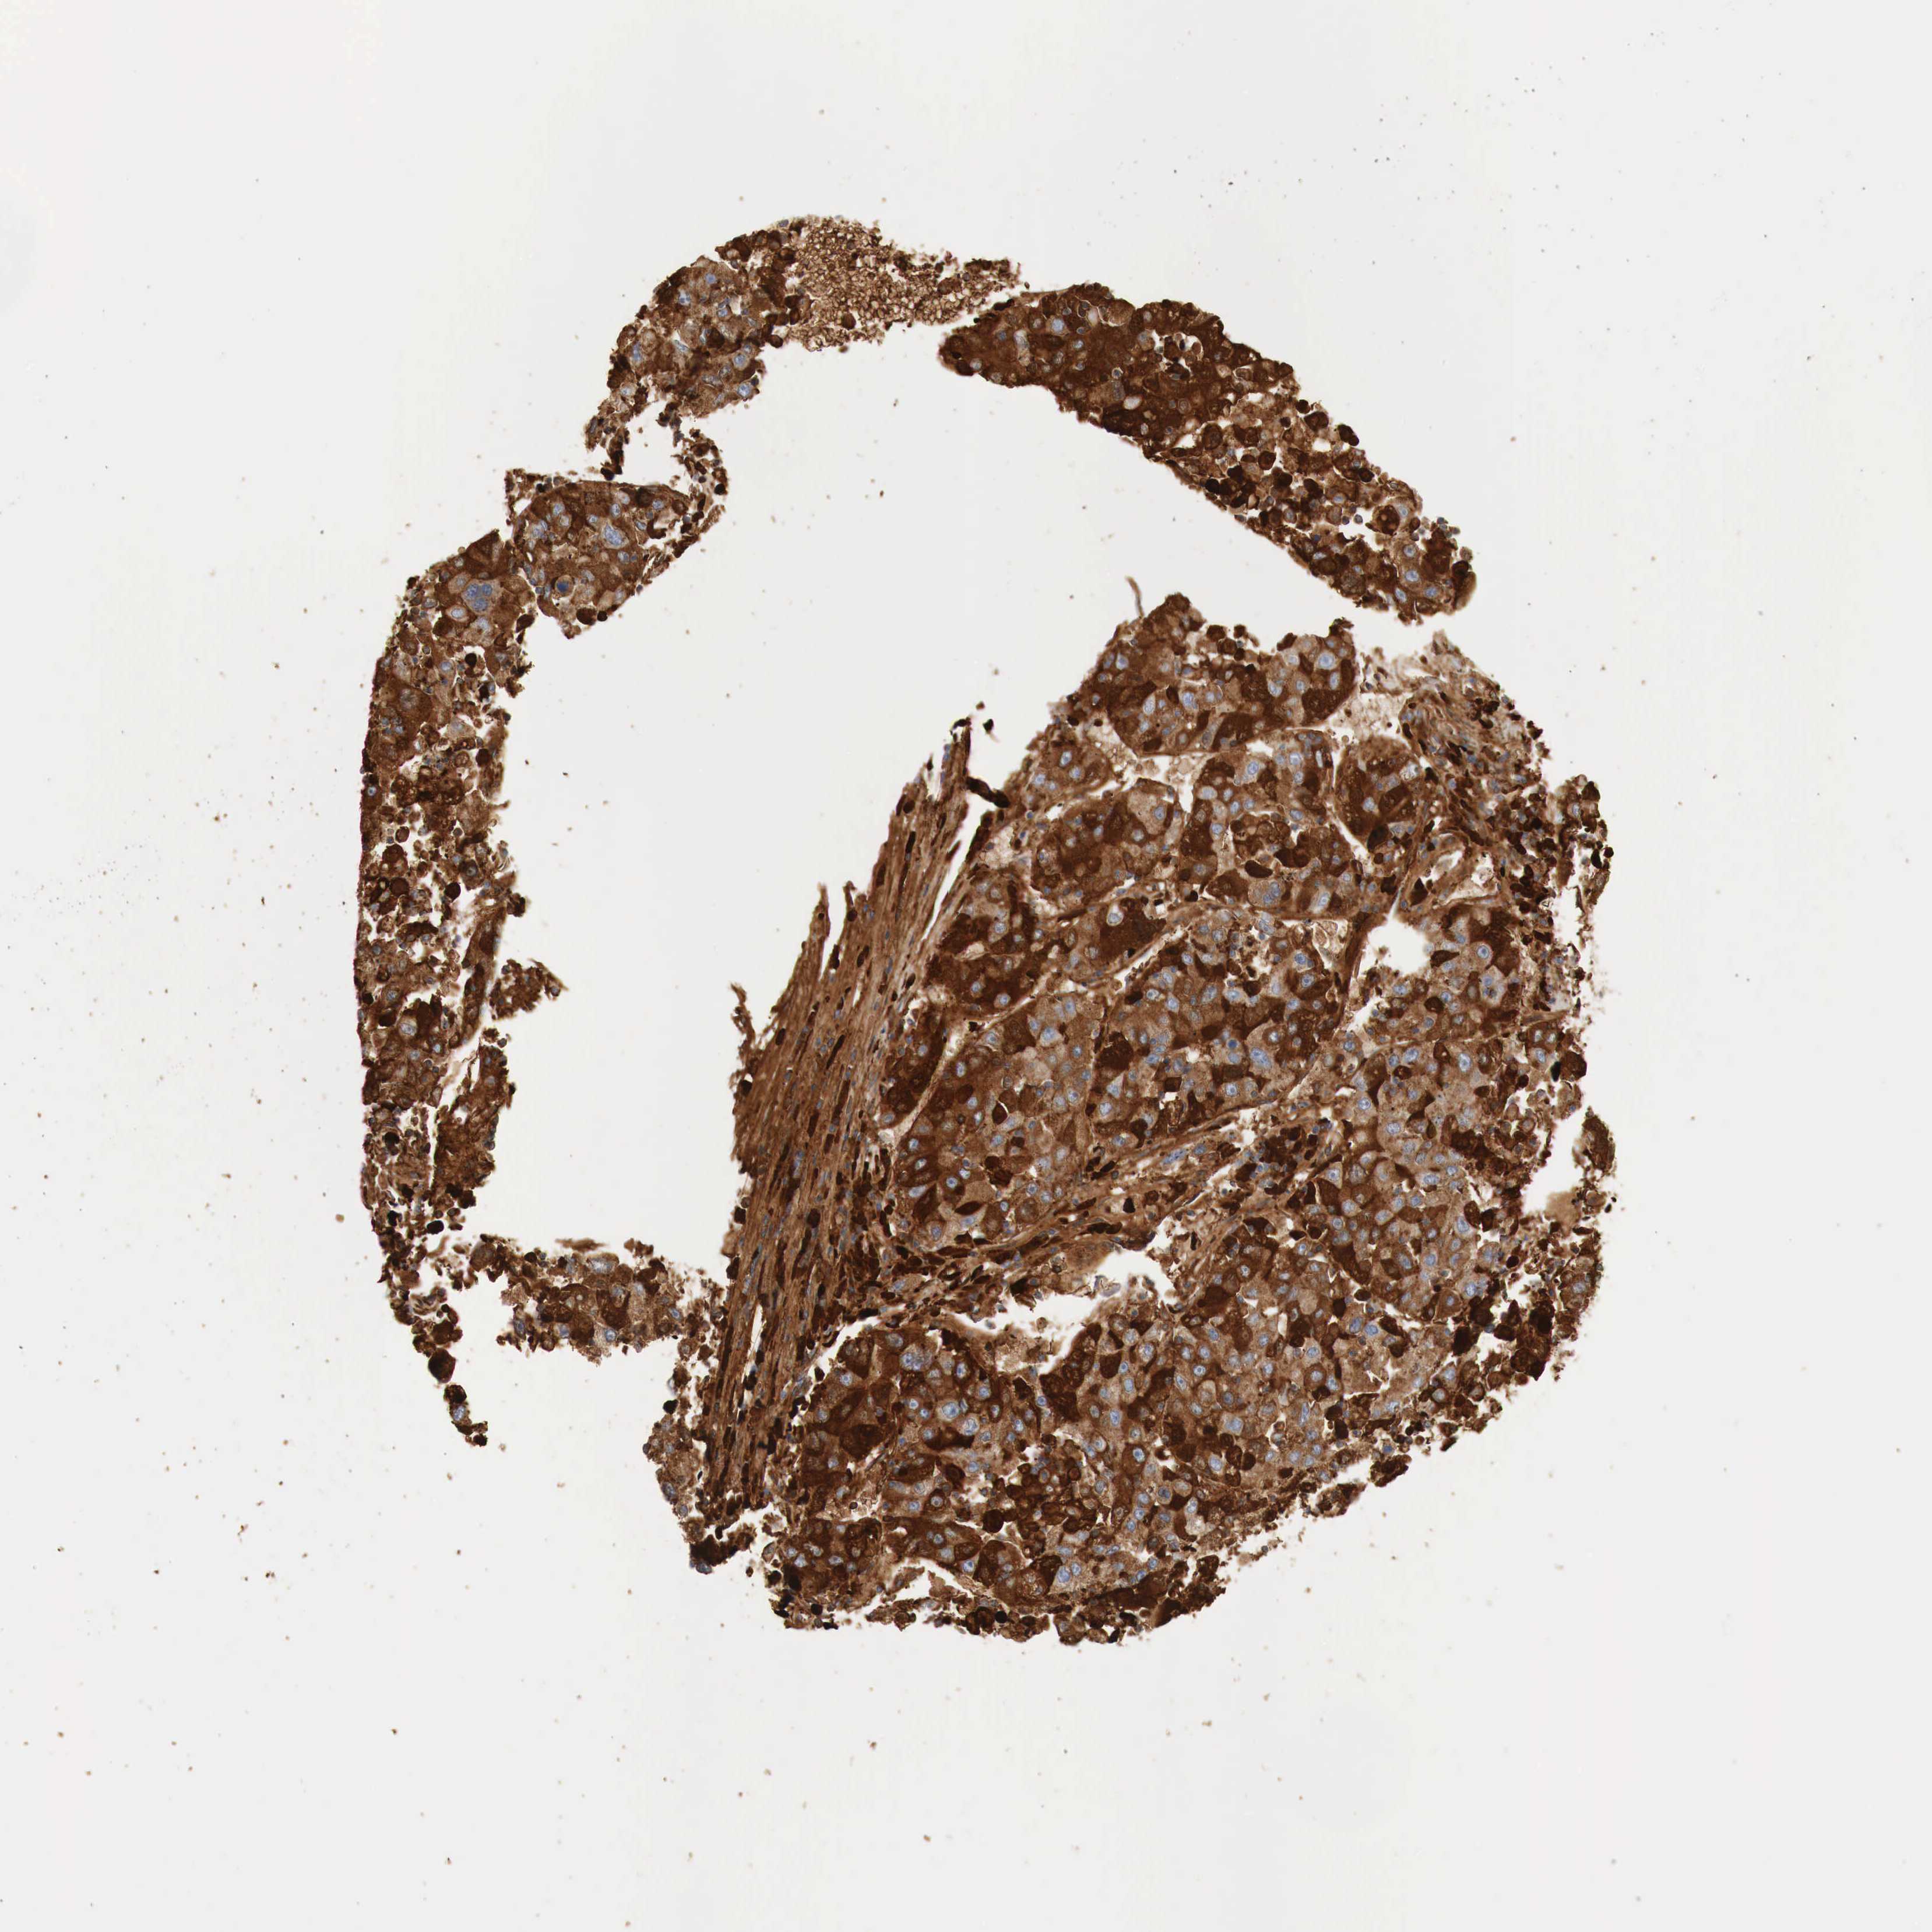

LIVER CANCER - Protein expressioni

A mouse-over function shows sample information and annotation data. Click on an image to view it in a full screen mode. Samples can be filtered based on level of antibody staining by selecting one or several of the following categories: high, medium, low and not detected. The assay and annotation is described here.

Note that samples used for immunohistochemistry by the Human Protein Atlas do not correspond to samples in the TCGA dataset.

Antibody stainingi

Antibody staining in the annotated cell types in the current human tissue is reported as not detected, low, medium, or high, based on conventional immunohistochemistry profiling in selected tissues. This score is based on the combination of the staining intensity and fraction of stained cells.

Each image is clickable and will lead to virtual microscopy that enables deeper exploration of all samples and also displays staining intensity scores, fraction scores and subcellular localization as well as patient and tissue information for each sample.

Antibody CAB000050

Antibody CAB016533

Staining

High

Medium

Low

Not detected

Intensity

Strong

Moderate

Weak

Negative

Quantity

>75%

75%-25%

<25%

None

Location

Nuclear

Cytoplasmic/membranous

Cytoplasmic/membranous,nuclear

Carcinoma, Hepatocellular, NOS